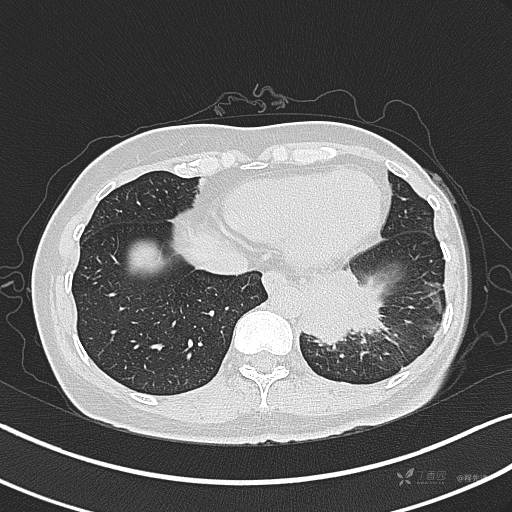

增强静脉期

静脉期CT值约84HU

CT值:平扫:31HU,动脉期:74HU,静脉期:84HU